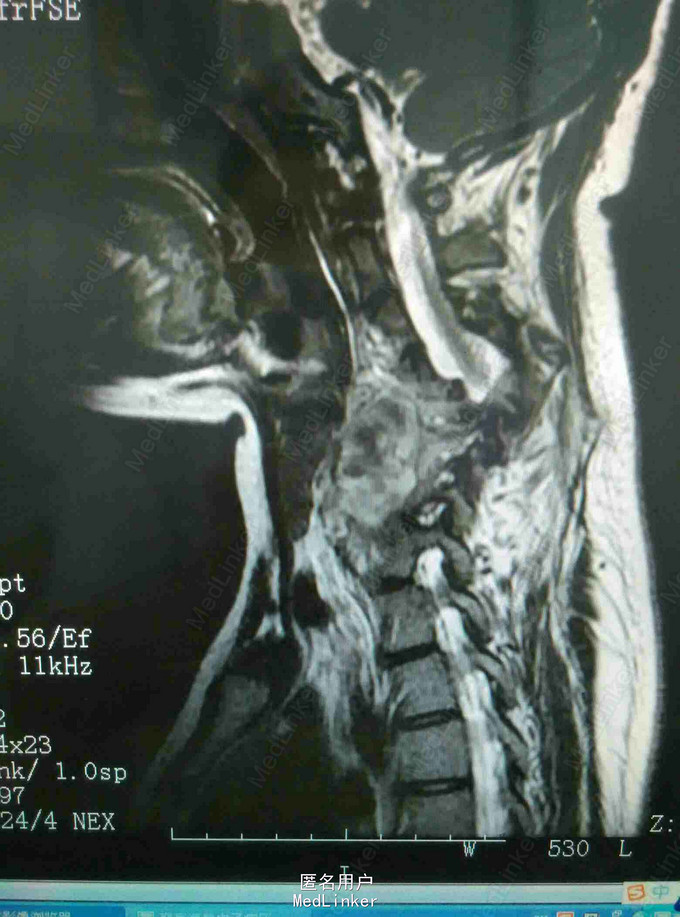

颈肩痛伴左侧肢体无力5月 患者青年男性,无明显诱因出现颈肩痛,性质钝痛,伴有左侧肢体无力,症状反复发作五月。于当地医院就诊查核磁提示颈椎结核,椎旁脓肿。患者二便正常,既往结核病史。

查体:颈椎生理弯曲消失,各棘突及椎旁压痛,胸腰椎生理弯曲不在,各棘突无压痛,椎旁无叩击痛。左侧肢体肌力降低,双侧Hoffoman征阳性,Babinski征阳性。 辅查:我院磁共振提示颈椎结核并椎旁脓肿,颈椎失稳。

诊断:颈椎结核伴椎旁脓肿 颈椎不稳 四肢不全瘫。 治疗:颈前路病灶清除植骨融合内固定术+Halos架固定,术后护肝抗结核治疗